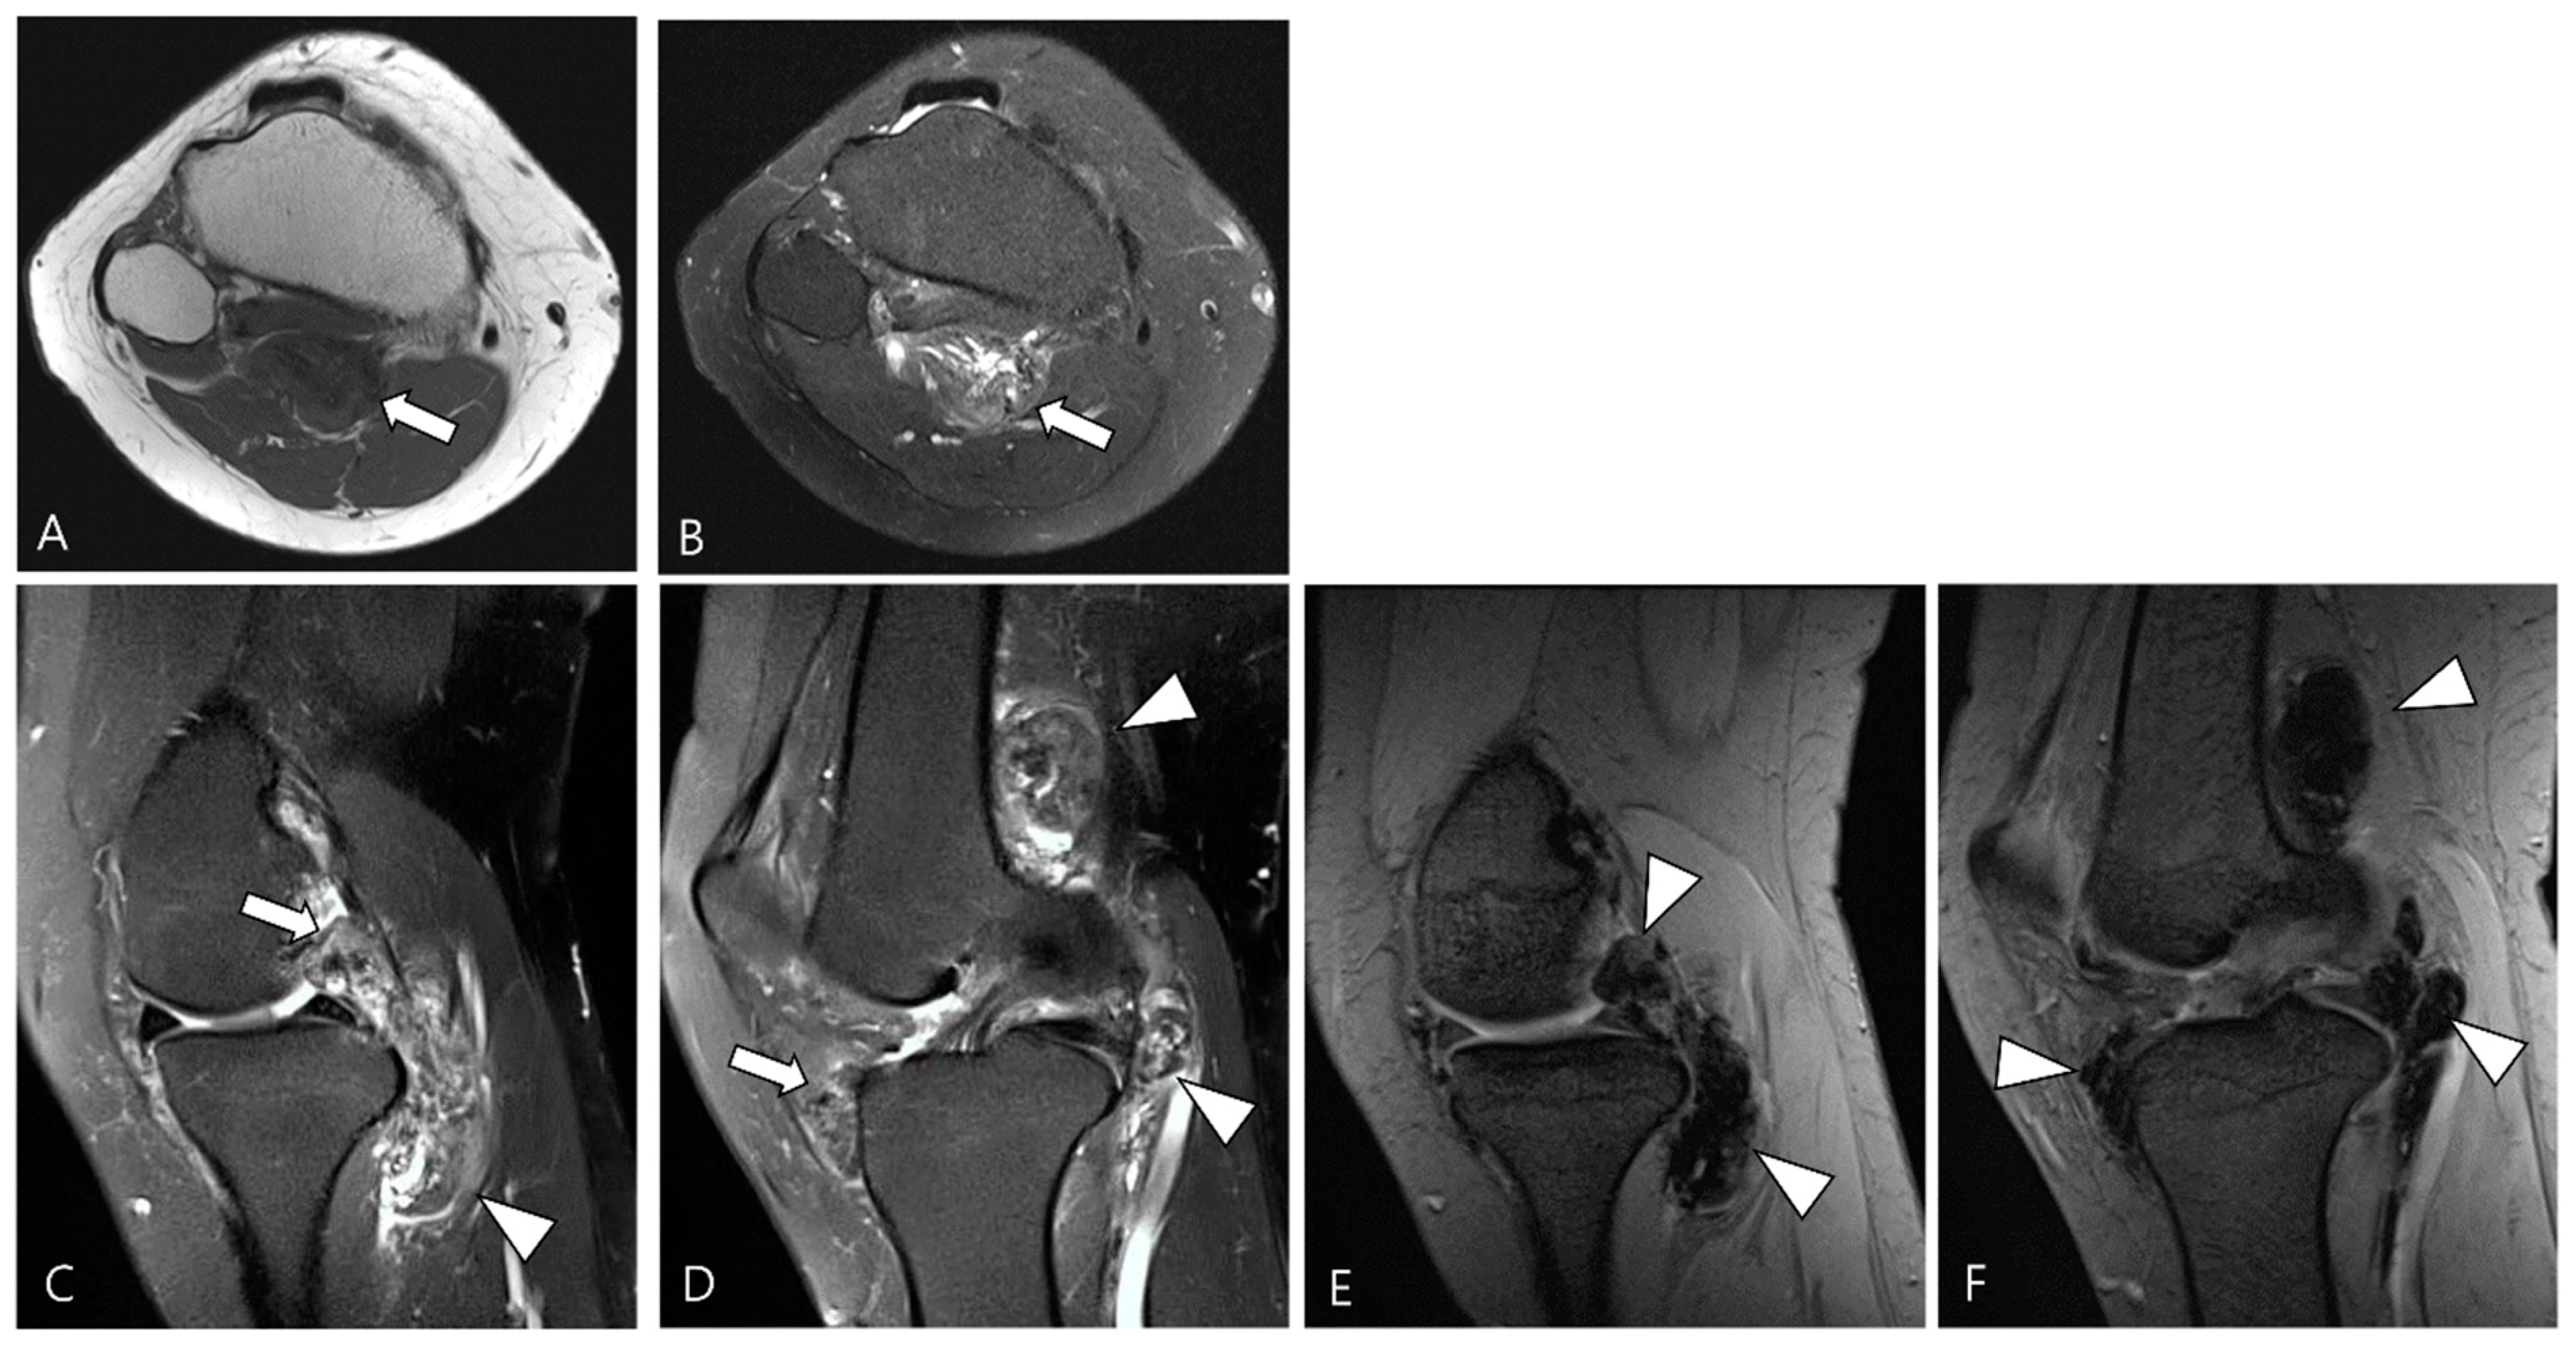

2.3. Morphological Findings for D-TSGCT

2.4. Relationship to Adjacent Structures of D-TSGCT

3.1. Differential Diagnoses of Intra-Articular D-TSGCT

3.2. Differential Diagnoses of Extra-Articular D-TSGCT